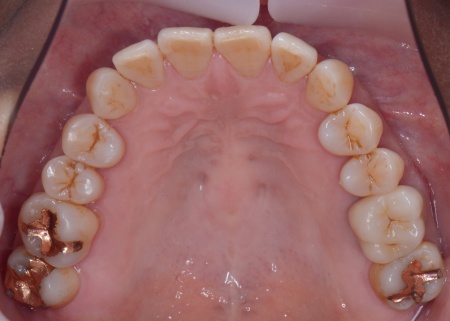

60代女性 重度の歯周病に対して歯周組織再生療法とインプラント治療を施した例

拝見したところ、上下左右の奥歯計8本(第1大臼歯、第2大臼歯)に重度の歯周病が認められました。

上左右の奥歯についても歯周組織再生療法を行い、歯をできるだけ残せるよう治療を進めました。

また、左上の奥歯は虫歯を取り除いたあと、歯の形を整えて型取りを行い、最終的にジルコニアクラウンを装着しています。

段階的に治療を進め、すべての治療を終了しました。